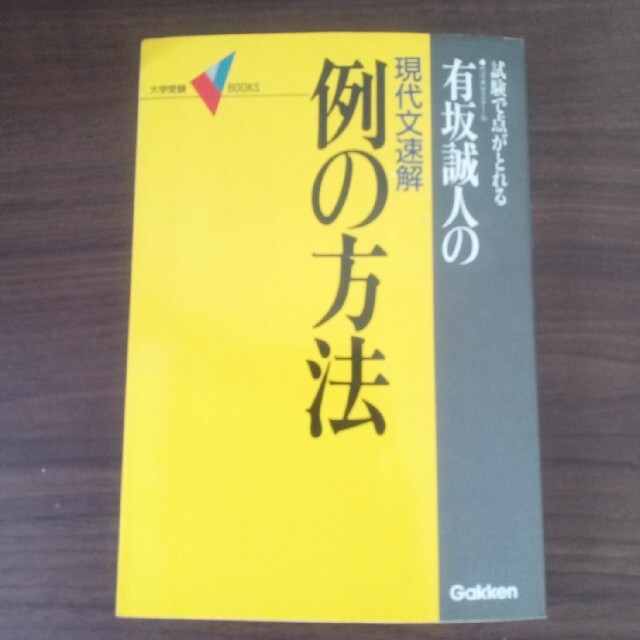

■商品名■

心臓CTを活かす新しい冠動脈疾患診断戦略?こういう症例に活用する平山篤志

■出版社■

メジカルビュー社

■著者■

平山篤志

■発行年■

2010/02/19

■ISBN10■

4758301972

■ISBN13■

9784758301978

■コンディションランク■

非常に良い

コンディションランク説明

ほぼ新品:未使用に近い状態の商品

非常に良い:傷や汚れが少なくきれいな状態の商品

良い:多少の傷や汚れがあるが、概ね良好な状態の商品(中古品として並の状態の商品)

可:傷や汚れが目立つものの、使用には問題ない状態の商品

■コンディション詳細■

書き込みありません。江户川学園取手小学校 2022年受験実力養成問題シート1〜6集。子供の英語教材 【美品】 月刊ポピー。弊社基準で良よりコンデションが良いと判断された商品となります。水濡れ防止梱包の上、迅速丁寧に発送させていただきます。English A: Literature (Oxford Ib Diploma Programme) [ペーパーバック] Androulaki, Anna; Whitted, Brent。サピックス 2023年度 6年生 7月度入室組分けテスト 小6 SAPIX最新版。